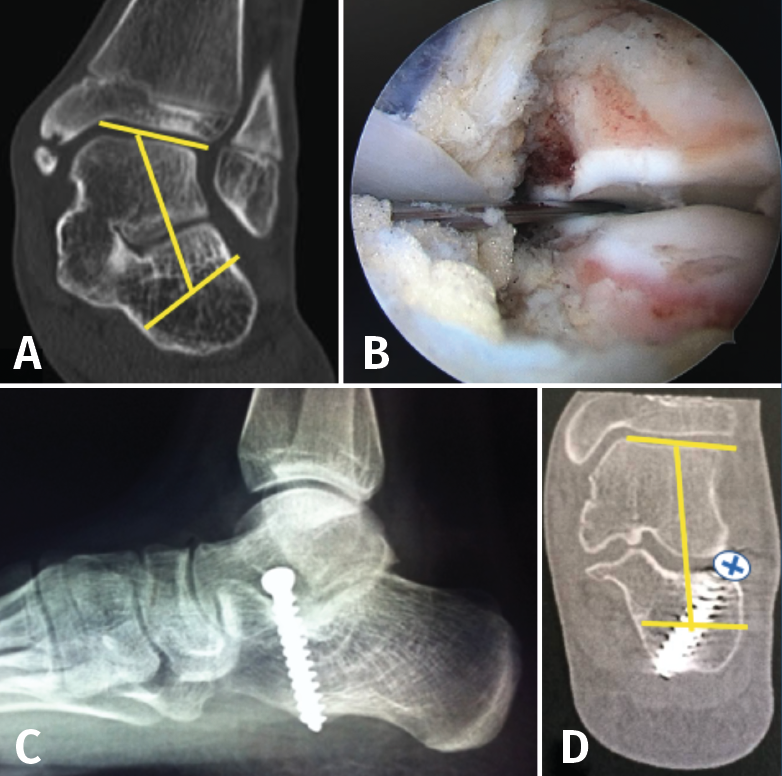

El tratamiento quirúrgico consiste en realizar la exéresis de la coalición de forma abierta con interposición de tejido. El tratamiento moderno consiste en resecar por vía endoscópica la CNC(17) o la TCC(18), sin interposición de tejido. La rápida movilización evita la recidiva. En caso de PPV de más de 20° se puede asociar el tratamiento del calcáneo stop, tras la resección de la coalición(18)(Figura 16).

Figura 16. A: valgo severo de retropié secundario a coalición talocalcánea; B: tras resección completa por vía artroscópica de la coalición, se verifica la movilidad subastragalina, al realizar varo-valgo del talón; C: colocación de calcáneo stop, para corregir el valgo del retropié; D: tomografía axial computarizada de control, donde se visualiza resección de la coalición y corrección del valgo del retropié.